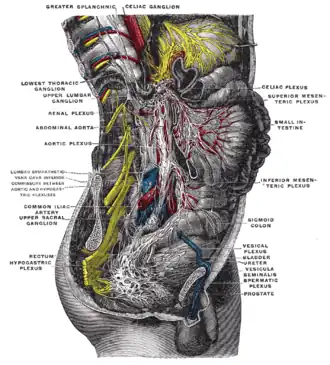

Abdominal portion of the sympathetic trunk, with the celiac and hypogastric plexuses.

Abdominal portion of the sympathetic trunk, with the celiac and hypogastric plexuses. -